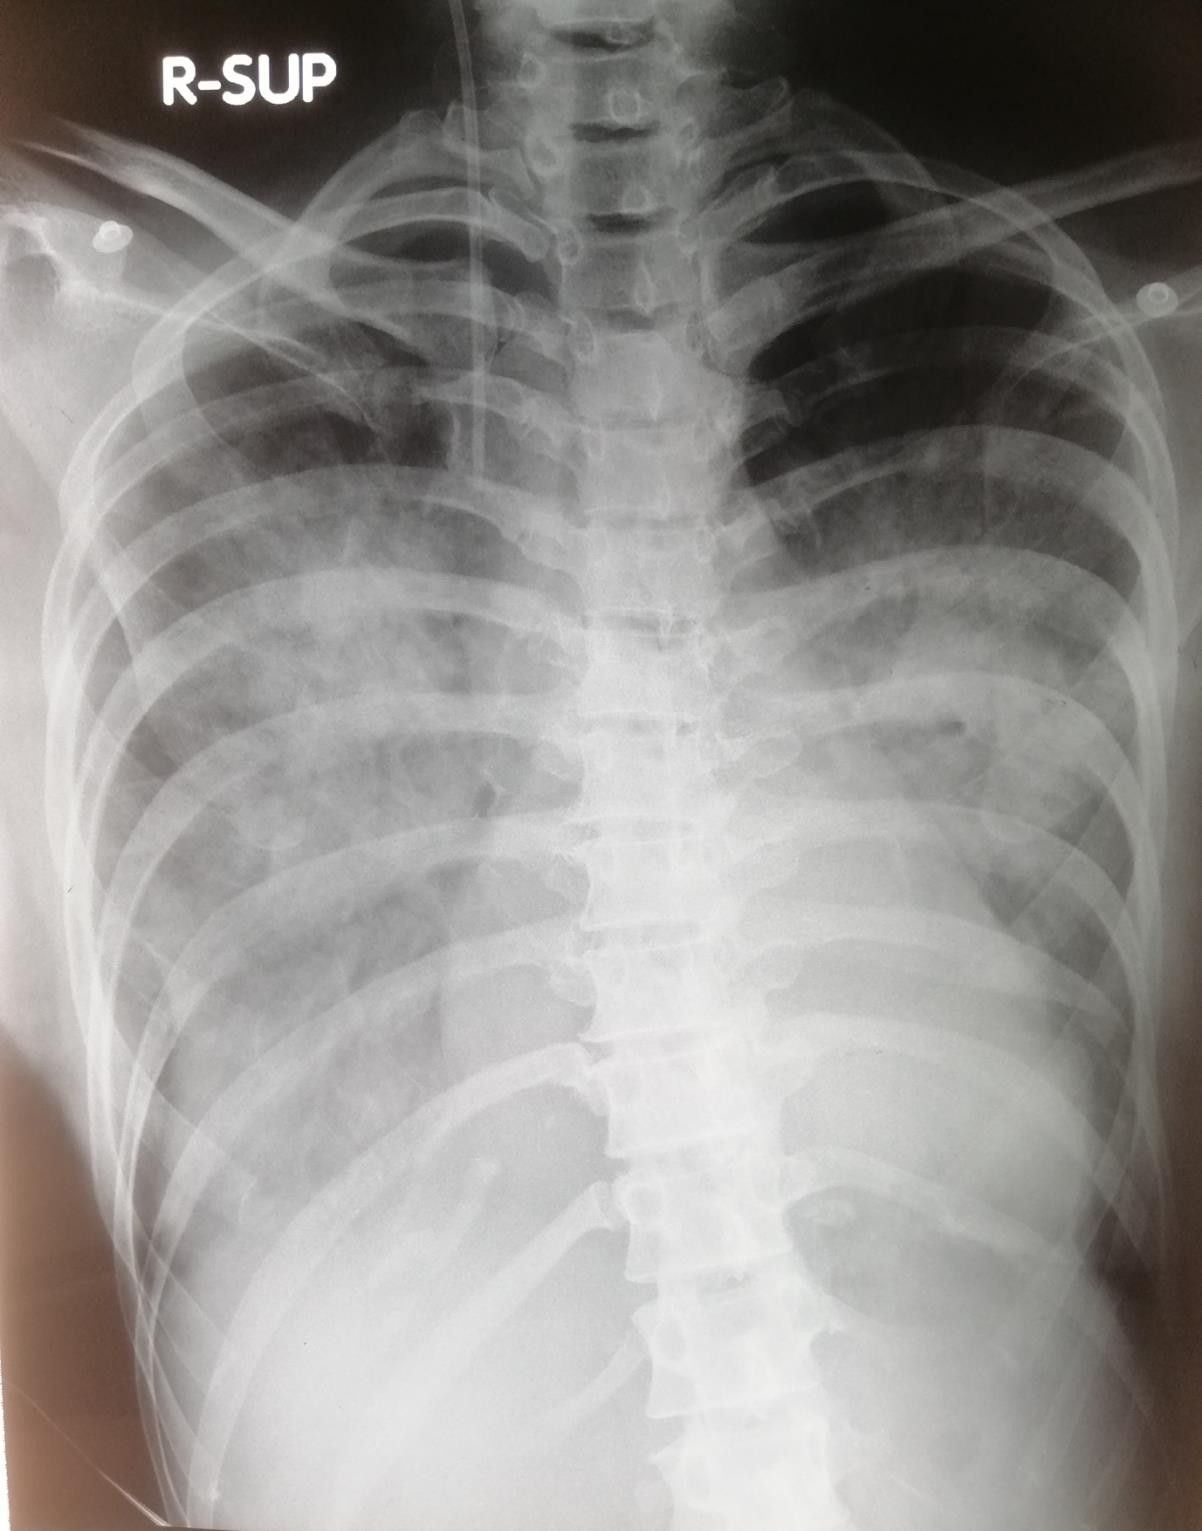

Once the intubation plan was in place the transport ventilator was checked and pre-set with recommended settings for ‘type 2’ or ARDS type Covid pneumonia. The reason was the index case had tachypnoea, severe respiratory distress, widespread B lines on lung ultrasound, diffuse infiltrative opacities on both lung fields in the chest x ray and he improved with application of positive pressure support placing him in type 2.2